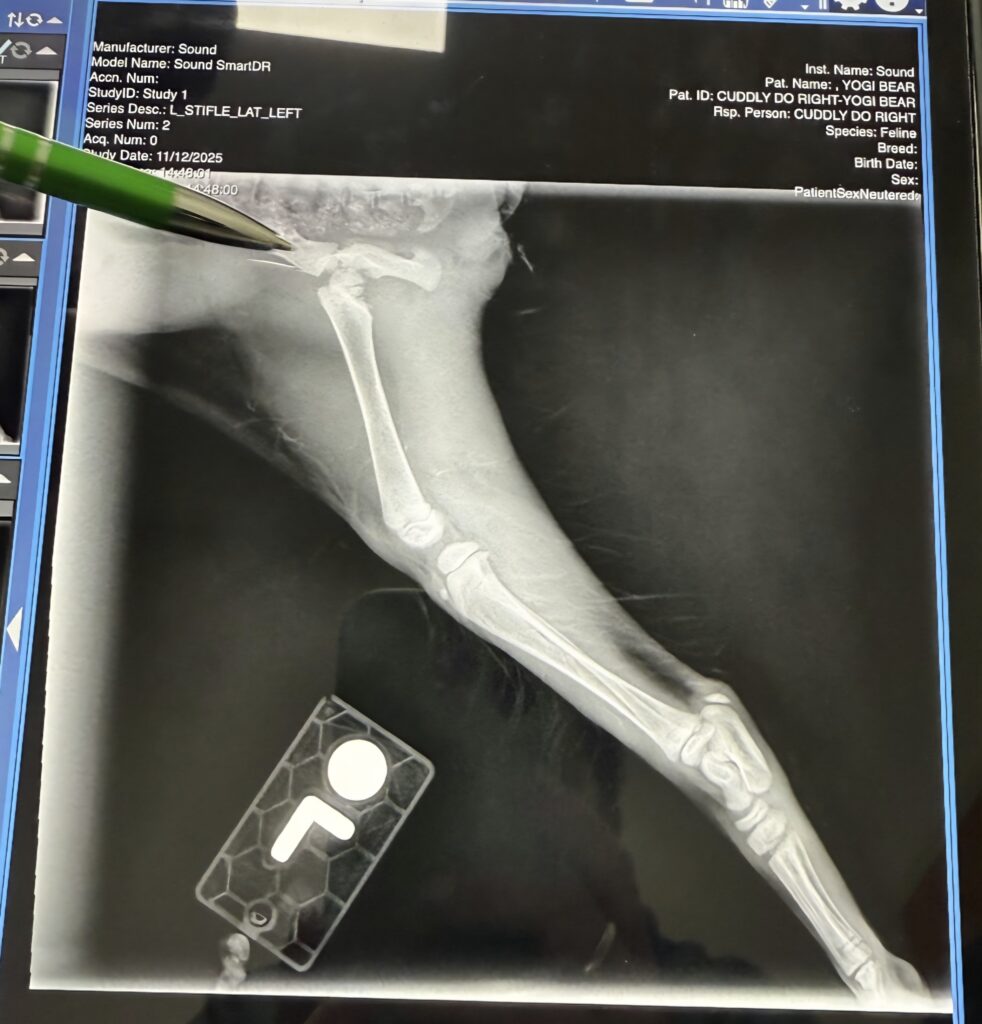

The question of what’s causing her to react in pain to having her left foot/leg touched and why she needs human assistance to support her tail end when she potties was answered, too. For the grand sum of $385, Yogi got her first poke and prod, a vaccination, some pyrantel… and a couple xrays. She has a fractured and dislocated femur. 😱

Yogi will need surgery to resolve this. The first estimate we’ve received is $1500-1800. We are seeking a second estimate and will update you about that and everything else related to Yogi Bear!